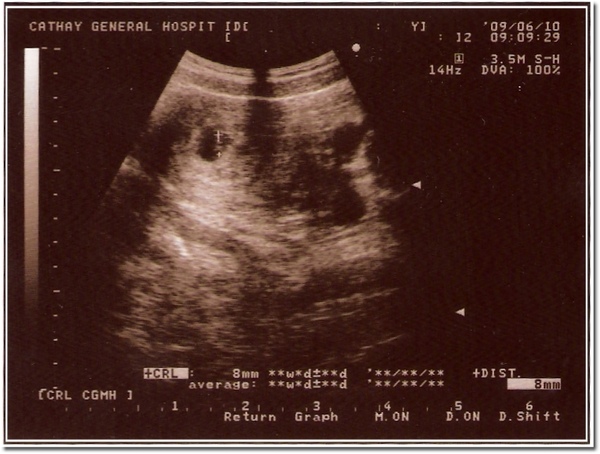

98/06/10 第二次照超音波,大約7週多

醫師說一閃一閃的是心臟

不過我是怎麼看都不懂,哈哈efb50fe2.gif

980610.jpg